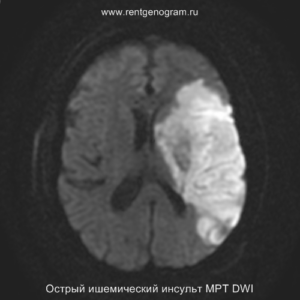

На МРТ и КТ изменения могут отсутствовать. На МРТ у некоторых пациентов могут быть первые признаки ишемии. На DWI область ишемического повреждения может быть видна через 2,5 часа после появления первых симптомов.

С 4-5 часов на DWI должны быть заметны признаки ишемического поражения, которые представляют собой «ядро» инфаркта.

Острая фаза (6 — 24 часа)

В течение острого этапа на МРТ и КТ выявляются все морфологические признаки ишемического инсульта. Область острого ишемического инфаркта визуализируется как зона ↑Т2, ↑Flair, ↑DWI и ↓Т1 ↓ADC. Можно обнаружить тромб в артерии. На КТ в остром этапе также чётко дифференцируется поражённая область, представляющая собой участок с потерей дифференциации мозговых структур и снижением их плотности. Контрастирование в остром периоде не показывает патологических участков с накоплением контраста.